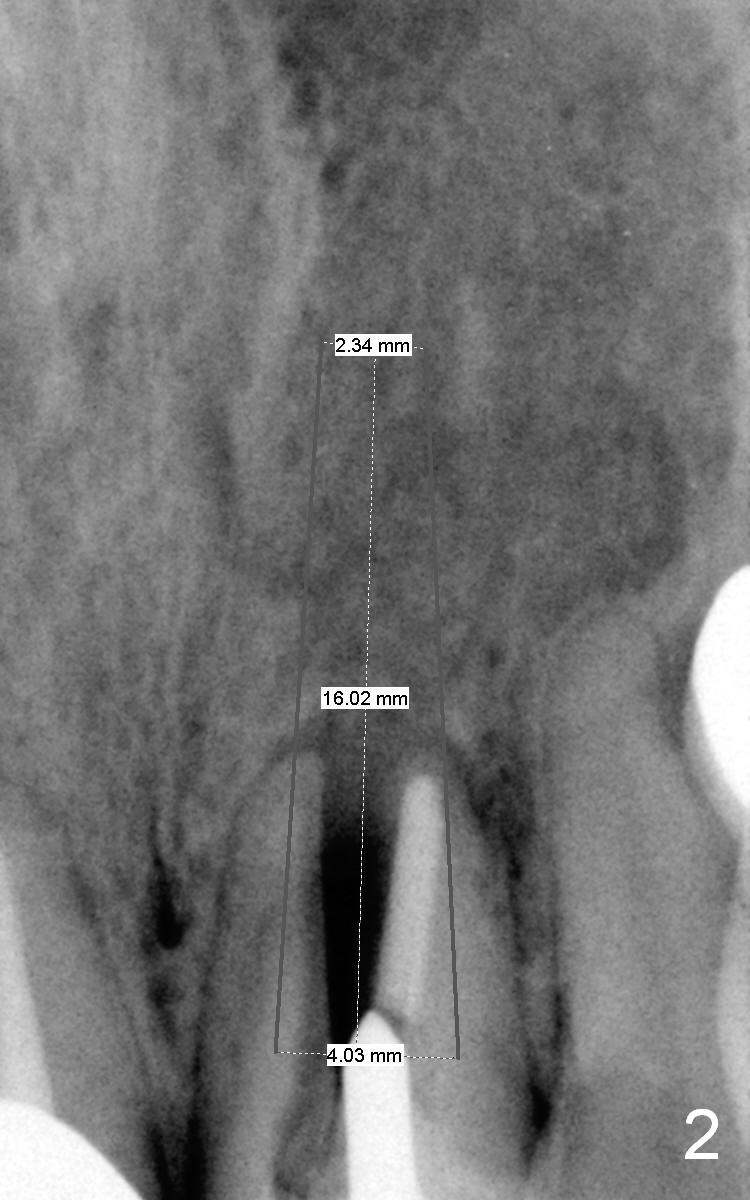

A 64-year-old woman (XP) has multiple restoration, requesting implant replacement for the loose upper left central incisor (Fig.1). It is asymptomatic, although there is labial swelling with purulent discharge from the labial gingival sulcus. The labial plate must have been absent. After granulation tissue removal and socket treatment with no antibiotic, place a 4x16 mm implant in a correct position (Fig.2). Place Osteogen tape against the labial defect and then bone graft with a small piece of gauze in the implant well. Since the lady is small in stature with possible osteoporosis and X-ray is particularly dark (Fig.2 (Fig.1 has been lightened in brightness)), use low voltage when taking new X-ray. Take preop photos to show labial swelling and purulent discharge from the labial gingival sulcus.